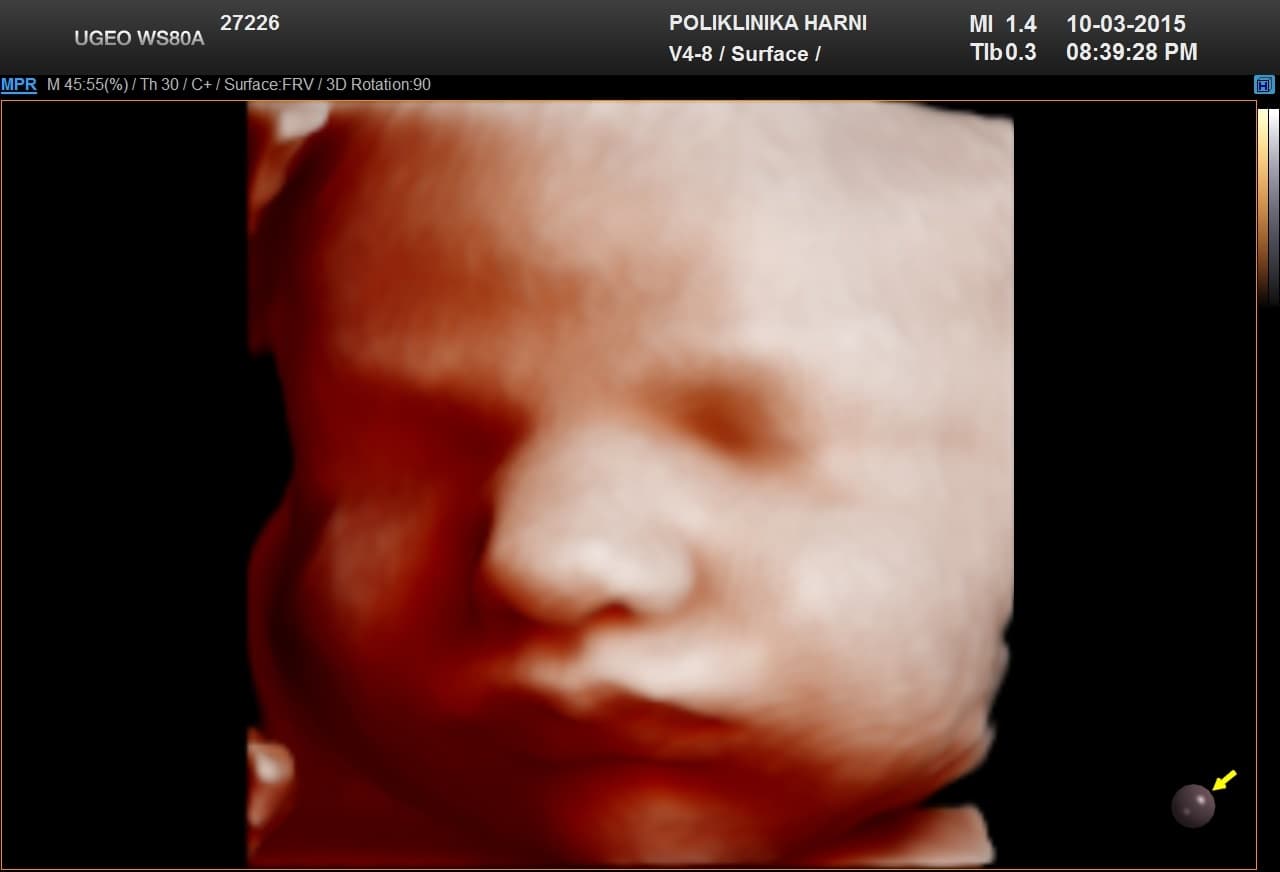

Na zadnjem kongresu ISUOG – International Society of Ultrasound in Obstetrics and Gynecology, predstavljene su nove softerske opcije za 5D ultrazvuk WS80A Elite, čiji dizajn i tehnološke inovacije potpisuje Samsung. Nova dijagnostička rješenja mogu se primjenjivati kako u porodništvu, tako i u ginekologiji, a predstavljaju korak više u jasnoći prikaza, dijagnostici i dijagnostičkom povjerenju.